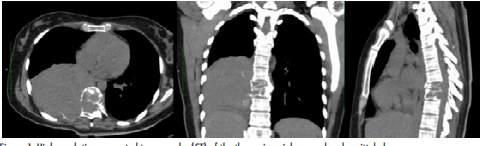

All blood tests were within normal parameters. Diagnostic imaging (Figure 1) showed a right paraspinal tumor in posterior mediastinum at the level of the eighth and ninth thoracic vertebra, with calcifications involving bone structures, posterior arch and expansive osteolytic lesions; a decrease in the vertebral bodies of T8-T9 was observed in bone window.

High resolution computed tomography (CT) of the thorax in axial, coronal and sagittal planes.

Figure 1: High resolution computed tomography (CT) of the thorax in axial, coronal and sagittal planes.

Source: Document obtained during the study.